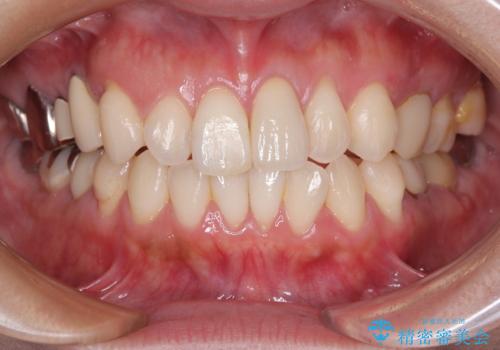

食べ物がはさまりにくくなり、冷たいものがしみる症状もなくなり、大変満足していただきました。